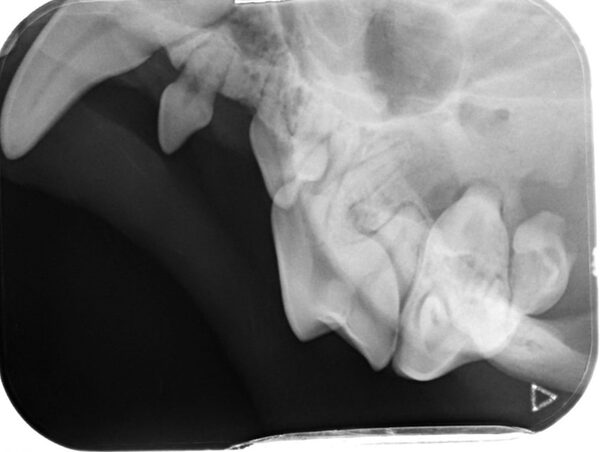

Das wahre Ausmaß zeigte sich allerdings erst nach ausführlicher Untersuchung in Narkose. Das Dentalröntgen und die Sondierung zeigten, dass bereits große Teile des Kieferknochens durch die Parodontitis verursachenden Bakterien zerstört wurde (die gelbe Linie zeigt an, wo der Kieferknochen sien sollte, die rote zeigt an wieviel Knochen bereits zerstört wurde). Dieser Knochenschwund ist leider irreversibel und in diesem Endstadium hilft nur noch die Extraktion.

Leider nicht. Beim genaueren Betrachten fiel auf, dass das Zahnfach stark aufgetrieben und entzündet war. Die beiden Zähne waren schwer erkrankt und dadurch aus dem Zahnfach geschoben worden. Im Vergleich ist ein gesunder Eckzahn im Röntgen dargestellt.